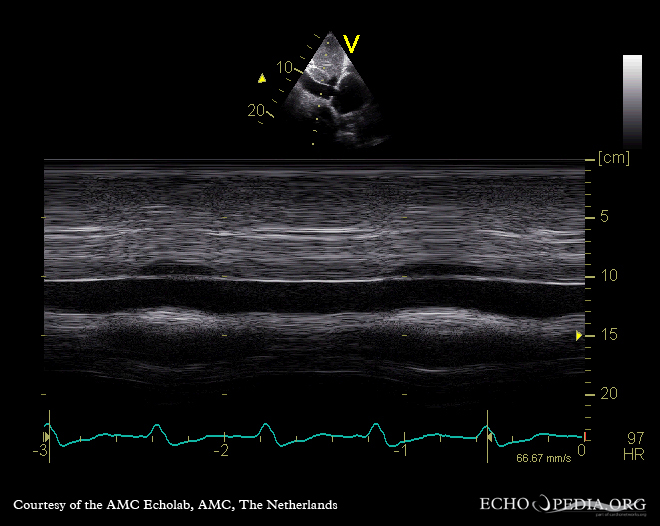

폐고혈압이 의심되는 경우, 심장 초음파 검사를 시행한다.[12][13][58] 도플러 심장 초음파의 메타 분석은 우심도자술 결과를 예측하는데 각각 88%와 56%의 민감도 및 특이도를 보고했다.[60] 따라서 도플러 심장 초음파 검사로 폐고혈압의 존재를 시사할 수 있지만, 우폐동 카테터 삽입술이 PAH 진단의 금본위적 표준으로 남아있다.[12][13]

심장 초음파 검사는 선천성 심장병을 감지하여 폐고혈압의 원인을 파악하는 데에도 도움이 될 수 있다.[12]